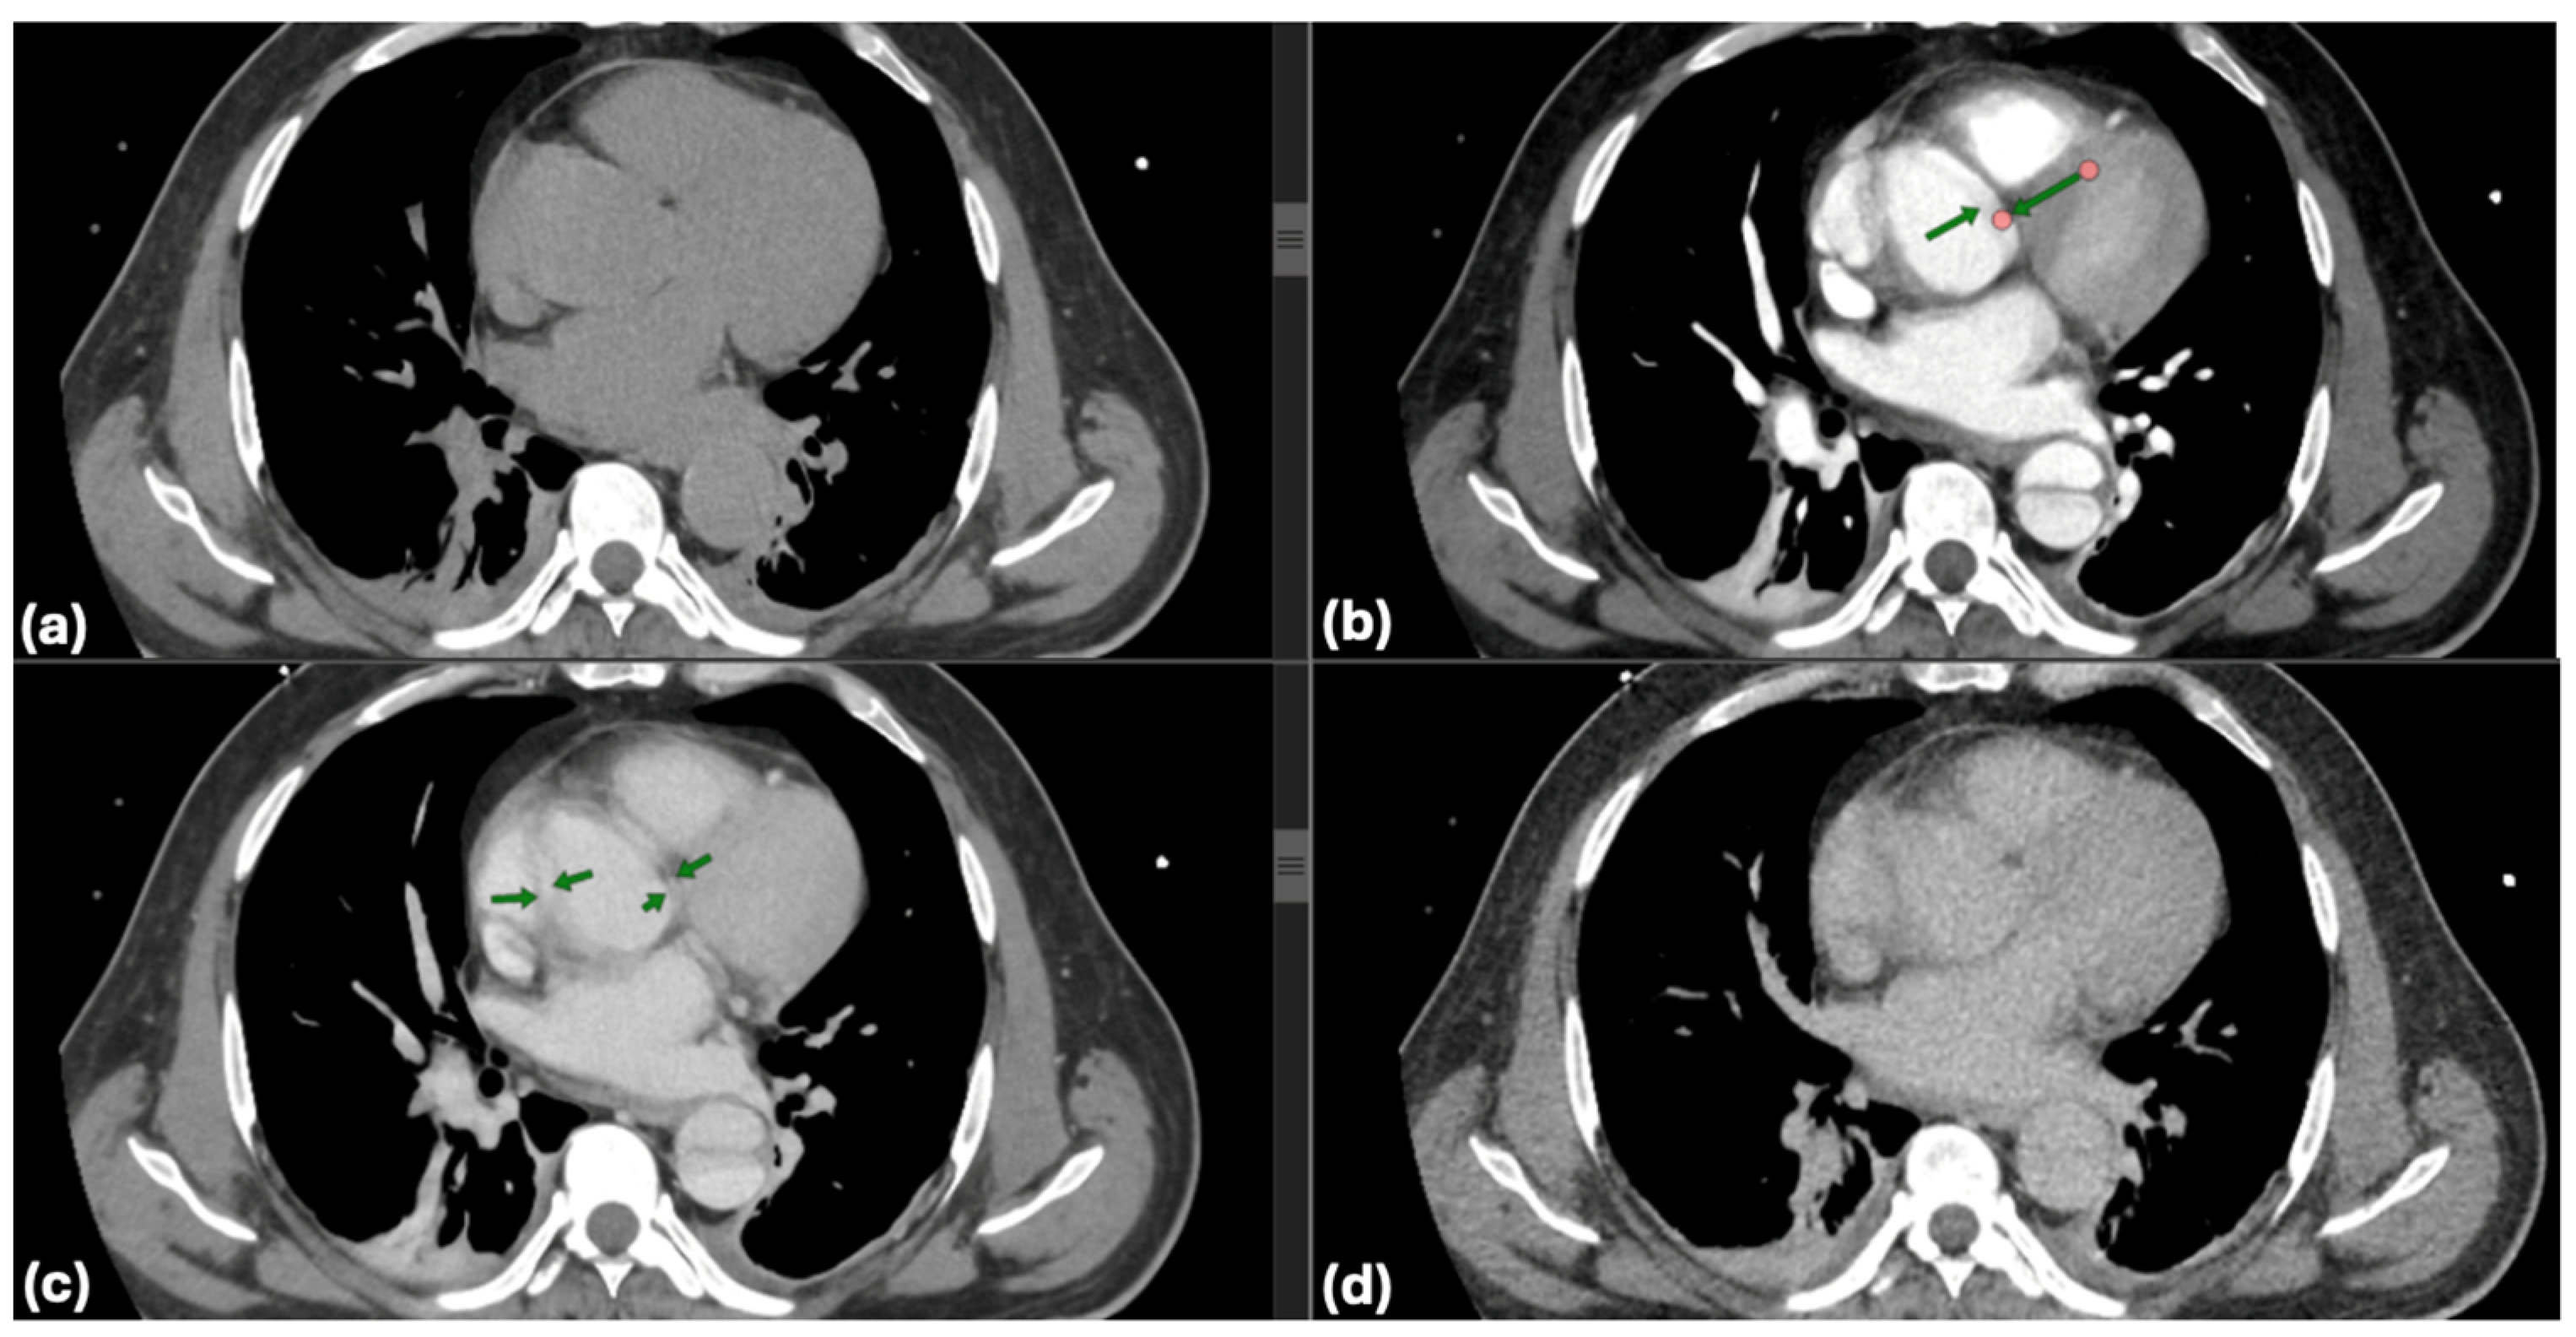

All patients received TTE upon admission. The assessment was conducted on left ventricular ejection fraction (LVEF), the presence of pericardial effusion, and wall motion abnormalities. The dimensions of the aorta and the presence of aortic valve pathology were recorded. CTA was conducted on all patients to verify the diagnosis of dissection, determine the extent of dissection (including the ascending aorta, aortic arch, and descending aorta), and assess for complications such as periaortic hematoma, rupture, or involvement of visceral arteries. Scans utilized a 128-slice CT scanner with contrast enhancement to delineate both true and false lumens. One of the critical aspects of evaluating aortic pathologies is the accurate visualization of the aortic lumen and wall structures through CT imaging. However, non-gated CT scans are susceptible to pulsation artifacts, which can obscure essential details and lead to diagnostic challenges. Common pulsation artifacts observed in this study are illustrated in Figure 2.

Figure 2. Artifacts in non-gated computed tomography: pulsation effects in aortic imaging: common artifacts from pulsation in non-gated computed tomography (CT) imaging are highlighted with green arrows (b,c). These artifacts can obscure critical details of the aortic wall and luminal structure, potentially complicating the assessment of aortic dissections (a,d). Accurate interpretation requires recognizing and mitigating such limitations.